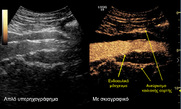

Αθήνα, 18 Φεβρουαρίου 2019 – Νέα, καινοτόμος

τεχνική για την αντιμετώπιση υπερνεφρικού ανευρύσματος της αορτής,

εφαρμόστηκε στο Ιατρικό Κέντρο Αθηνών, για πρώτη φορά στην

Ελλάδα, από το Θεοδόσιο Μπίσδα, MD, PhD, Αναπληρωτή

Καθηγητή Αγγειοχειρουργικής στην Πανεπιστημιακή Κλινική Muenster

Γερμανίας, Ενδοαγγειακό Χειρουργό, Φλεβολόγο, Κλινική Αγγειακής και

Ενδοαγγειακής...